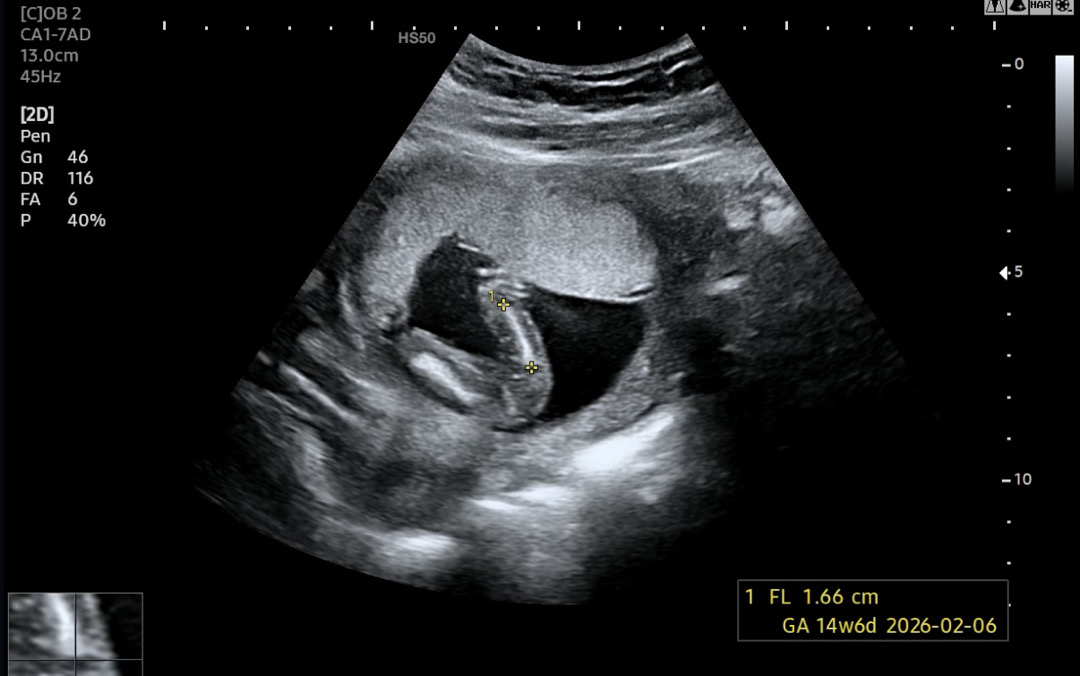

딸 맞을까요??

궁금합니다